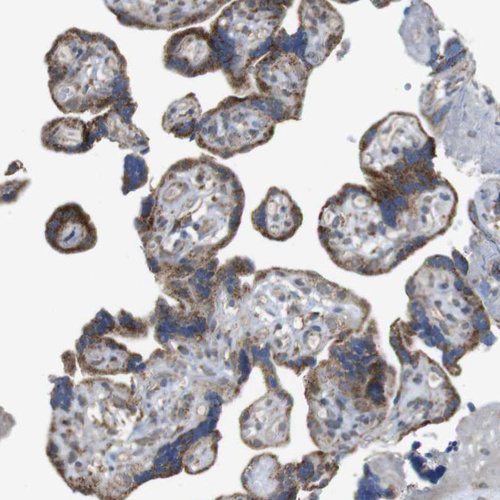

Immunohistochemical staining of human placenta shows strong cytoplasmic positivity in trophoblastic cells.